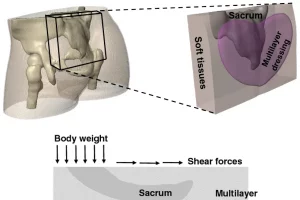

预防性骶骨敷料的多层结构设计模拟【Simpleware应用】

概述 骶骨是仰卧时发生压力性损伤(PIs)包括深部组织损伤的最敏感部位。预防性敷料通常设计用于减少摩擦、减轻内部组织剪切载荷、管理“微气候”,整体缓冲骶骨下软组织持续变形。 在本案例中,研究人员使用 Synopsys 公司的 Simpleware 软件基于 MRI 图像数据创建了臀部的三维有限元模型,用于研究仰卧或 45° 半坐卧在标准的医院泡沫床垫上时预防性骶骨敷料设计的生物力学性能。 亮点 通过模拟可以更好地了解医院的泡沫床垫对压力相关患者的损伤。Simpleware 软件快速准确的3D图像处理工作流程有助于缩短时间,增强对结果的信心,且可广泛应用于不同场景。持续性的研究可为选择和设计敷料以减少损伤的风险提供重要信息。 工作流 获取一名 28 岁女性受试者负重臀部的 76 张 T1 加权轴向 MRI 切片在Simpleware ScanIP 中进行图像数据分割和模型变形在Simpleware FE 中生成 3D 有限元模型,导出至 FEBio 的 PARDISO 求解器分析多层结构和持久的各向异性特性是对预防性敷料有利的重要特征 从 MRI 到三维图像处理 首先获取一名 28 岁健康女性受试者负重臀部的 76 张 T1 加权轴向 MRI 切片,使用 Simpleware ScanIP 分割出骨盆骨骼、股骨、骨骼肌和软组织。本研究应用相关的感兴趣区域(VOI)体积模型为 6.7×2×5.1 cm3 的立方体,包含骶骨和周围软组织。接下来,引入需要测试的3层预防性敷料,即聚氨酯泡沫层、无纺布纤维层和空气铺垫层,作为建模中的物理层。运用 Simpleware ScanIP 的三维编辑工具将模型化的敷料修整为典型的心形几何结构。 图:MRI切片和Simpleware […]